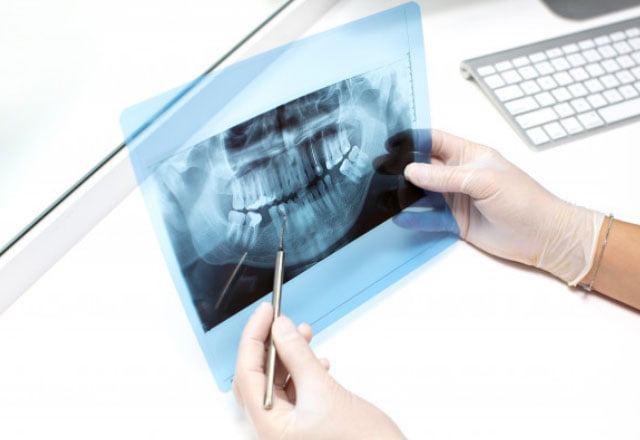

Oral Diagnoz & Radyoloji

Panoramik Film